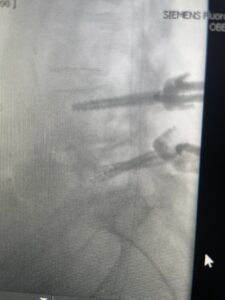

Fig 3: Lateral and AP fluoroscopic images demonstrating placement of pedicle screws for L4-5 fusion for spondylolisthesis.

Fig 6: AP and lateral fluoroscopic images demonstrating pedicle screw placement in L3-4 fusion for spondylolisthesis.